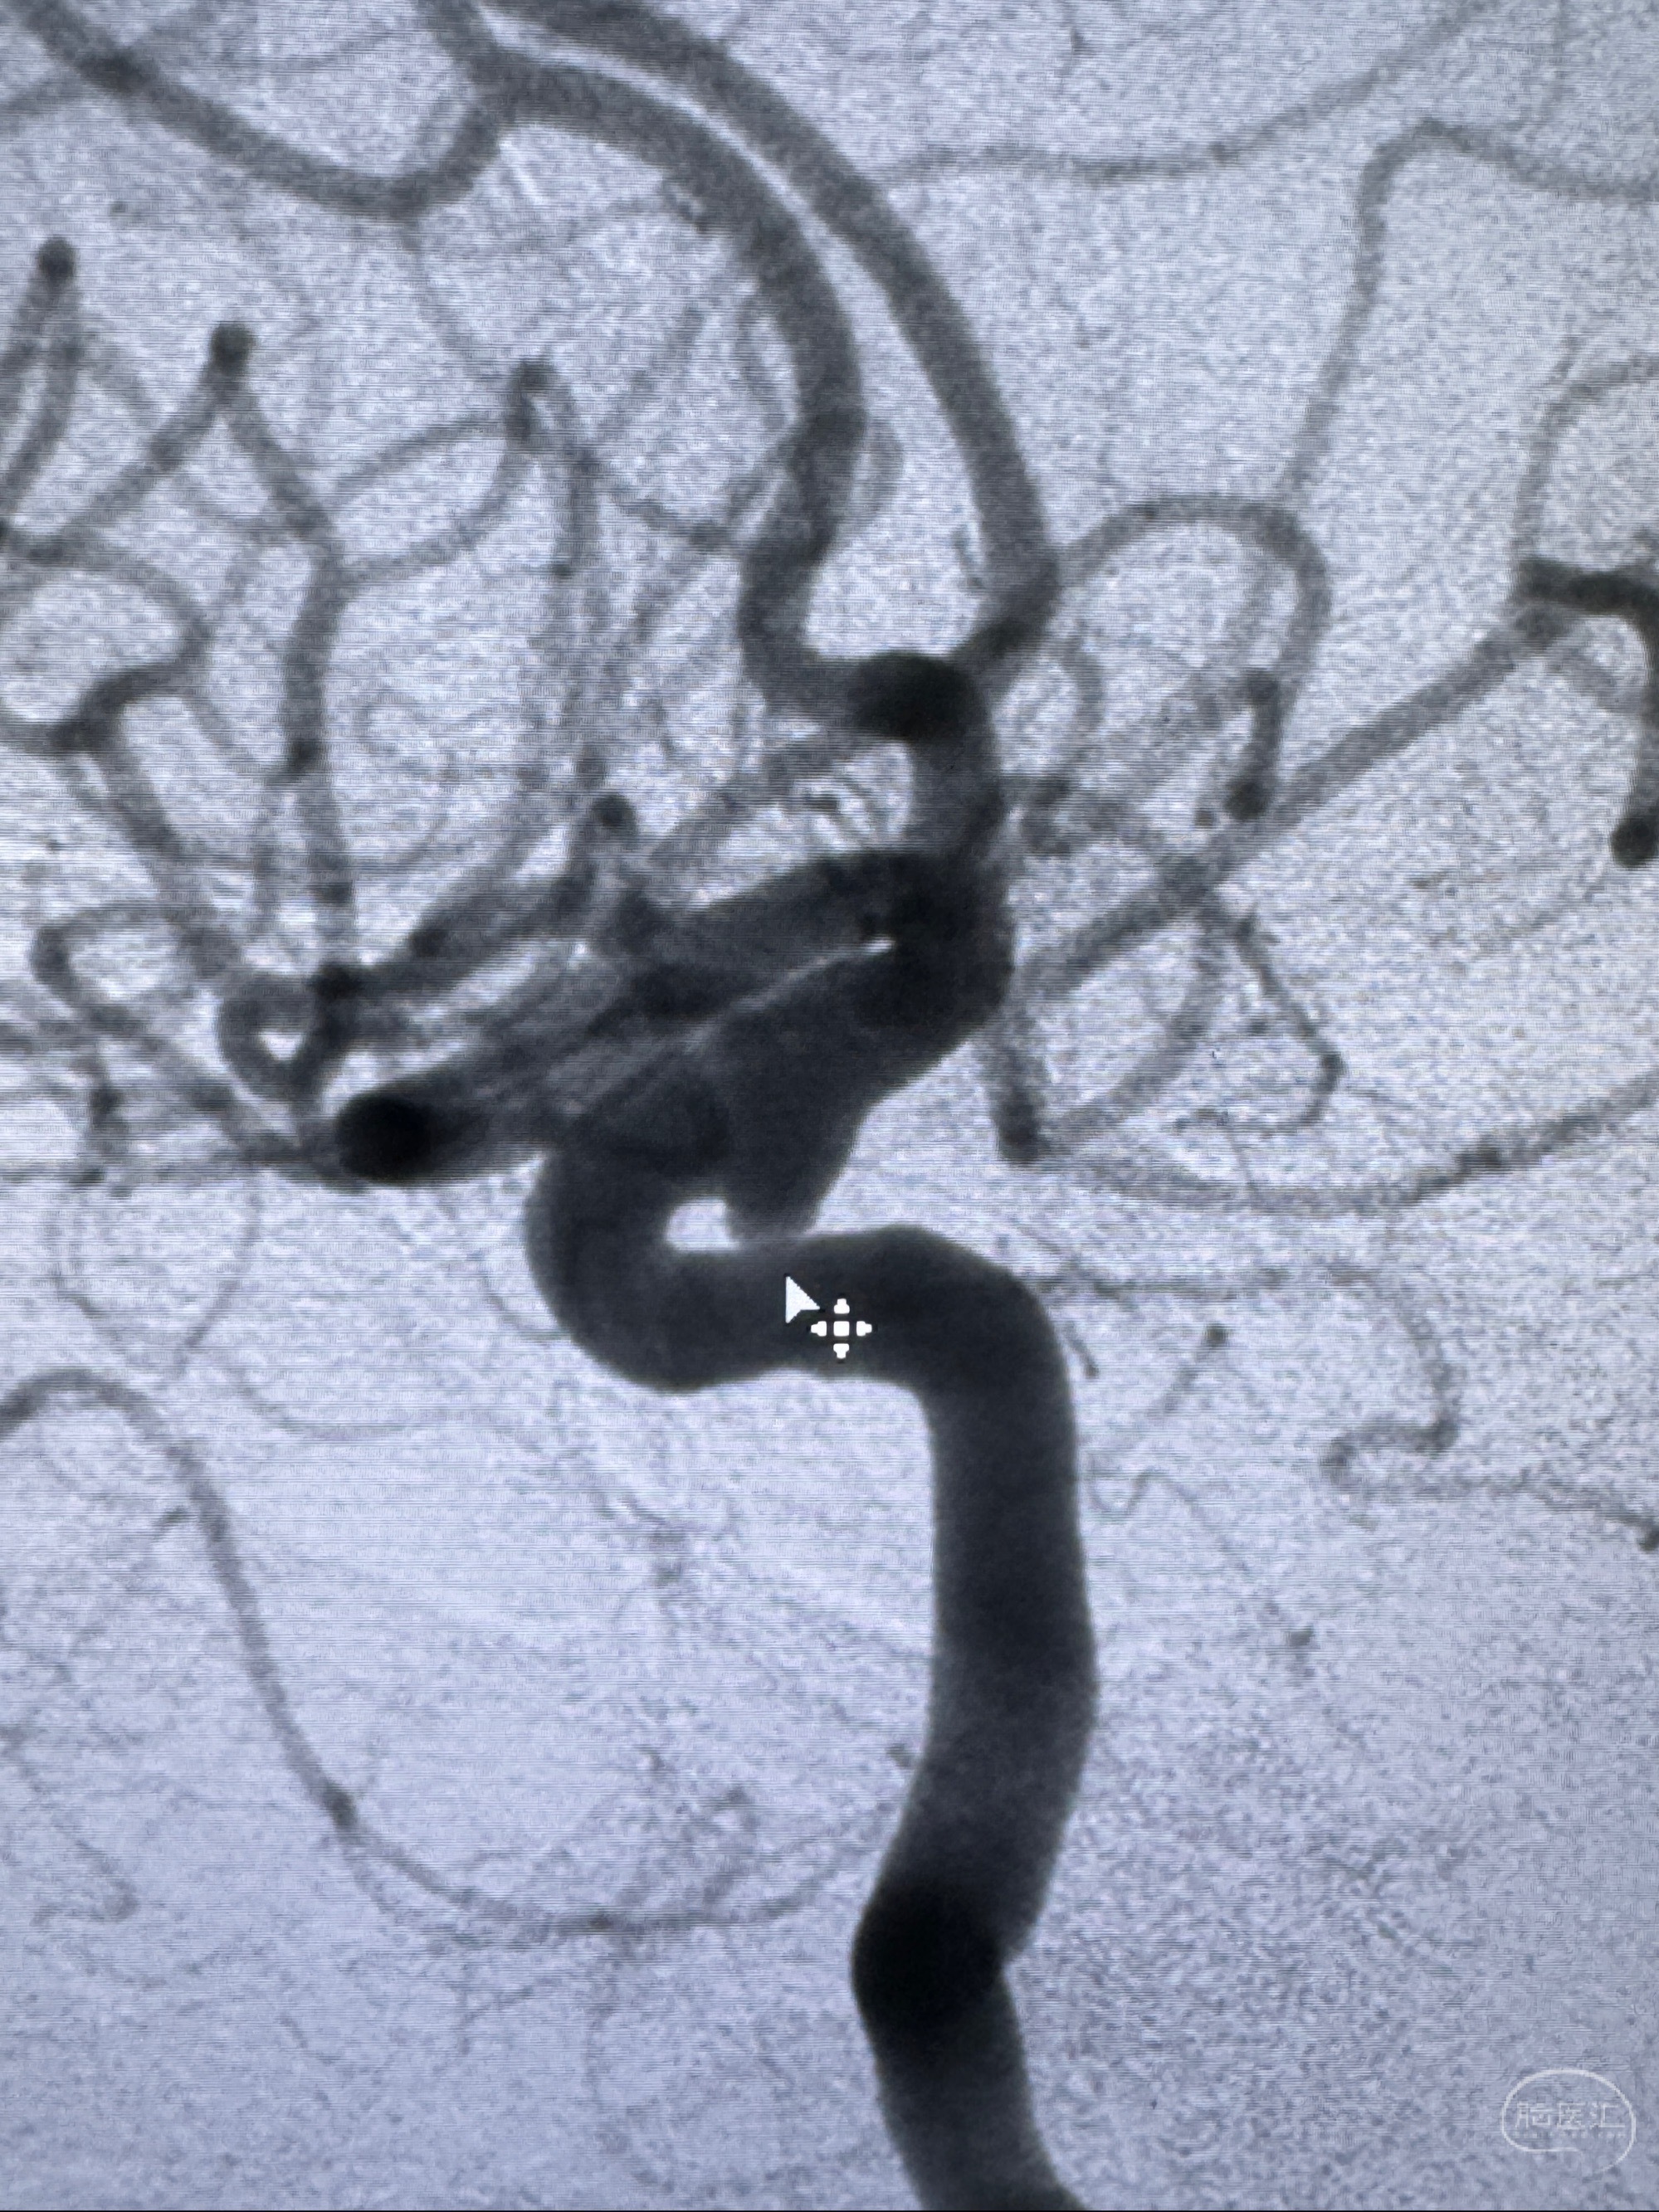

现病史:患者诉近4年来时有头痛发作,服用都梁软胶囊、氟桂利嗪对症治疗一月后症状改善,后头痛较少发作。近3月来患者头痛发作频率明显增加,约一月一次,为右侧偏头痛,胀痛,伴恶心呕吐,呕吐后症状可略减轻;遂于2023-11-01至蓝十字脑科医院就诊,查头颅MRI+DWI+MRA提示:左侧枕叶皮层下小斑片缺血或变性灶,右侧大脑前动脉A1段毛糙,显影淡、纤细,建议完善CTA;并于2023-11-03查头颅CTA提示:左侧颈内动脉C6段微小动脉瘤可能(约2mm),右侧大脑前动脉A1段纤细(对侧优势),左侧大脑中动脉提前分叉。现患者无明显不适,为求进一步诊疗颅内血管病变至我科就诊,收治入院。

2023-11-03 蓝十字脑科医院 头颅CTA:左侧颈内动脉C6段微小动脉瘤可能(约2mm),右侧大脑前动脉A1段纤细(对侧优势),左侧大脑中动脉提前分叉。

1.左侧颈内动脉瘤

治疗策略:

- 随访?

- 支架辅助治疗?